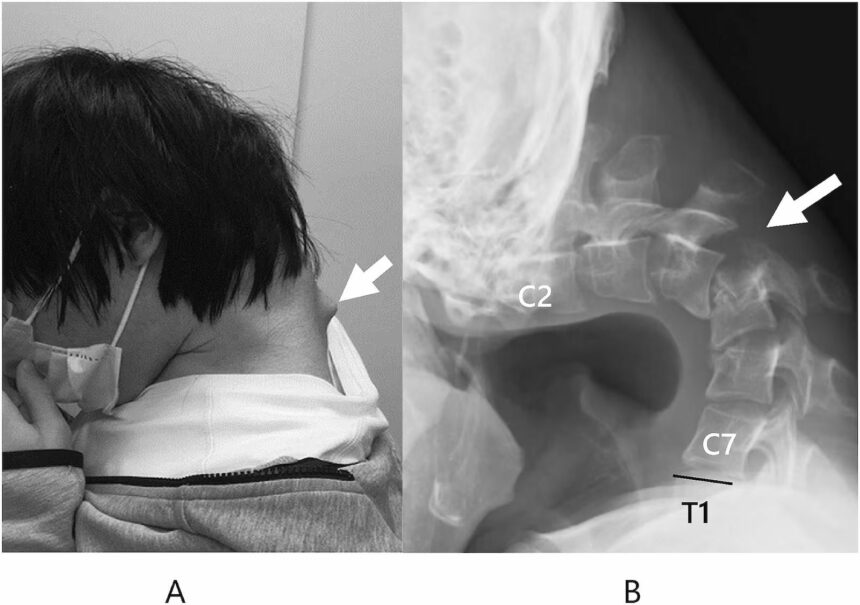

Os médicos revelaram que o paciente buscou ajuda após seis meses de dor intensa no pescoço e dificuldades para engolir. Além da limitação física, o jovem sofreu perda significativa de peso. Imagens mostram uma protuberância no pescoço decorrente de vértebras extremamente estendidas, além de tecido cicatricial na espinha cervical, resultado de anos na mesma posição.

O tratamento inicial consistiu no uso de colares cervicais para tentar estabilizar o pescoço. No entanto, o paciente relatou dormência e desconforto com o uso prolongado dos dispositivos, levando os médicos a optarem por cirurgia. O procedimento incluiu a remoção de vértebras danificadas e a inserção de hastes e parafusos metálicos para reposicionar a coluna.

Seis meses após a operação, o paciente foi capaz de sustentar novamente a cabeça, com melhora completa das dificuldades para engolir. Um ano após a cirurgia, não houve retorno dos sintomas. Os médicos classificaram o tratamento como bem-sucedido, embora ressaltando que parte do quadro pode ter origem em distúrbios do desenvolvimento ainda não identificados.